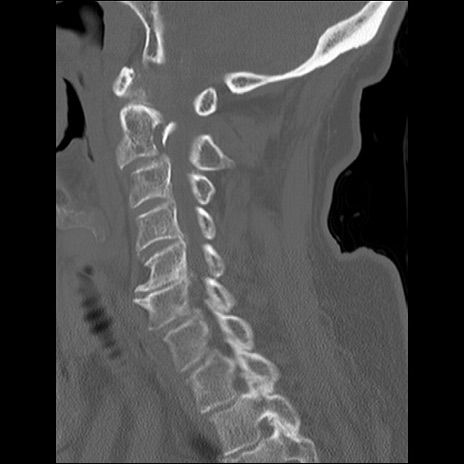

症例48 頚椎CT(矢状断像)

頚椎CT